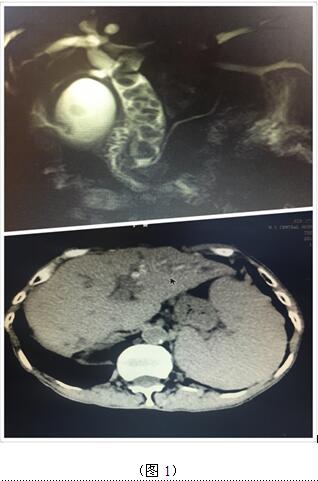

70歲高齡的曹奶奶是一個膽內膽管結石、膽總管結石、膽囊結石的高齡患者,由于結石部位多發(fā)(圖1),當地醫(yī)院多次住院治療,均建議開大刀切除部分肝臟;同樣患肝臟腫瘤的張爺爺,由于腫瘤位于肝臟尾葉,而且壓迫腹腔大血管(圖2),尋遍多家醫(yī)院都只能開腹手術切除,聽說衡陽市中心醫(yī)院腹腔鏡手術技術成熟遂慕名而來。肝膽外科周玖橋主任和李鑫副主任醫(yī)師仔細分析病情后決定為倆位患者行3D腹腔鏡手術。